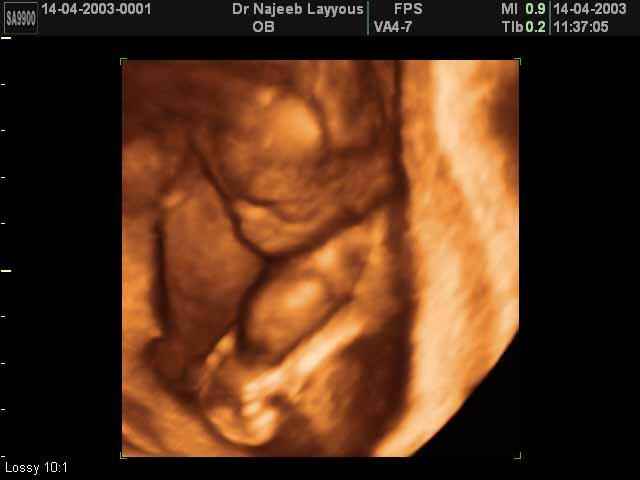

- Fetal Behavior Ultrasound Photos

Ultrasound Photos in 3D showing Fetal Behavior Inside the uterus | Dr N Layyous